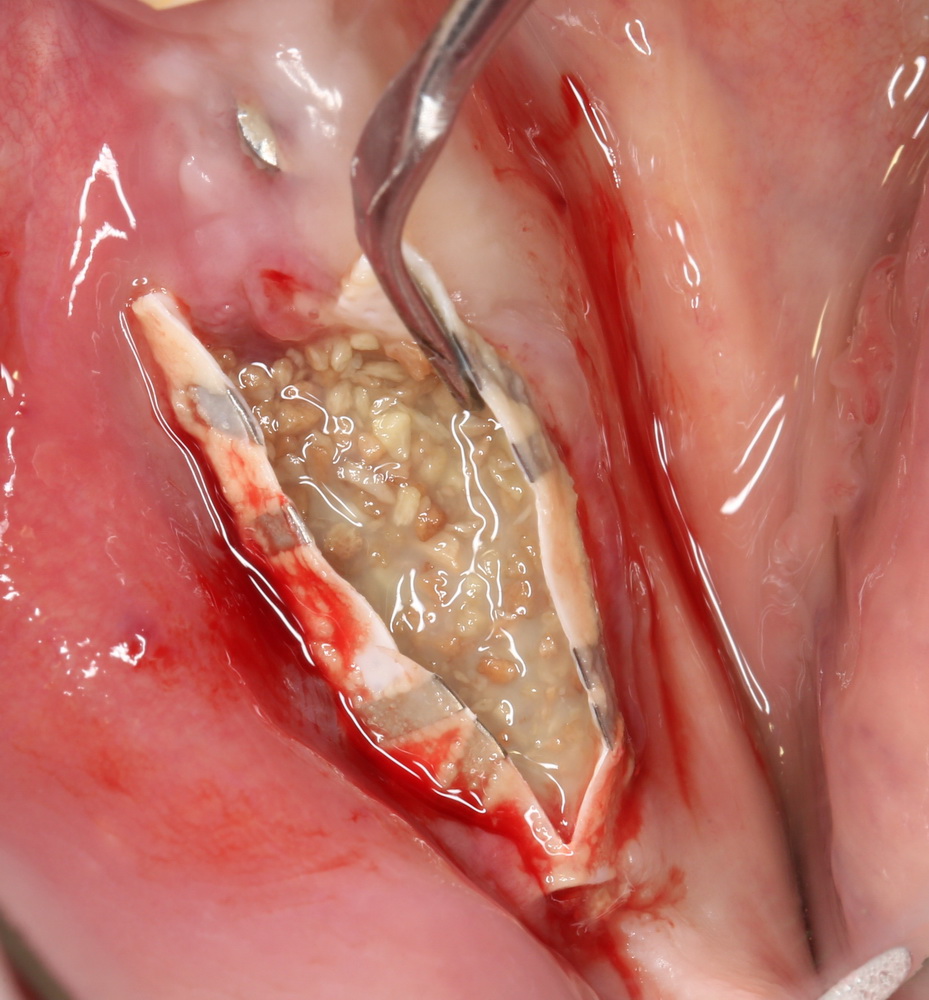

Так и в смеси с ксенотрансплантатами. Например, Geistlich Bioss:

Оптимальное соотношение — 50/50, но допускается и 30/70.

Затем укладывается и конфигурируется аутокостная стружка: